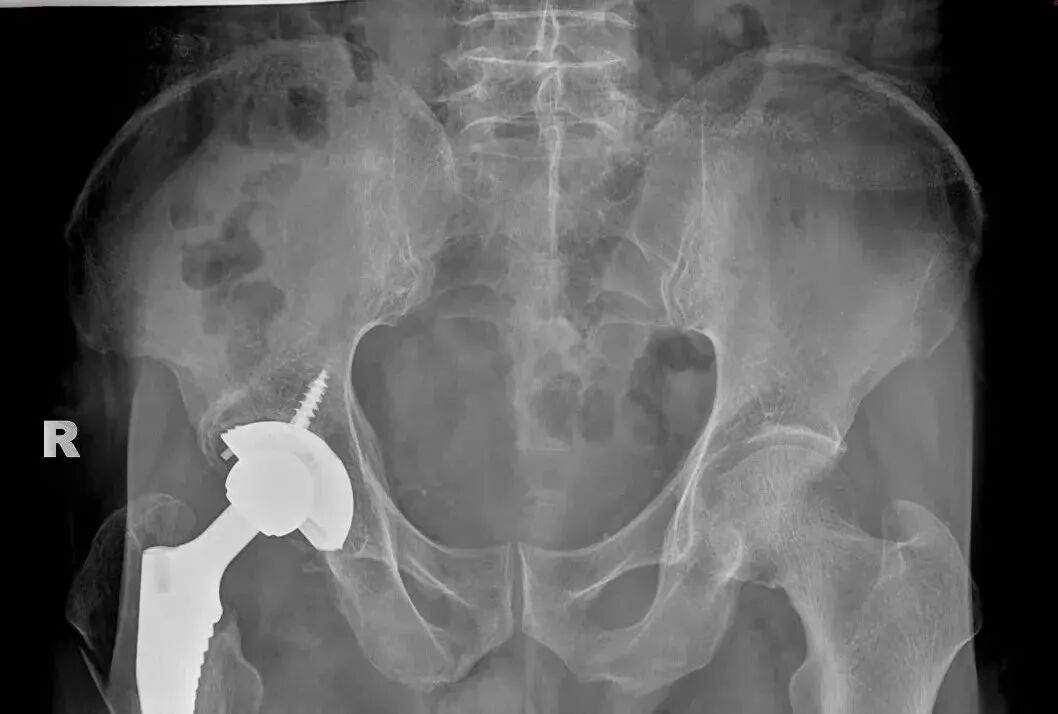

面对如此棘手的问题,骨一科团队创新性地与厂家合作,最终决定采用3D打印技术实现复杂髋关节精准化翻修。根据患者具体骨缺损形态,量身定制了个体化3D打印髋臼填补垫块及配套假体,并于2月8日成功为患者施行了“右侧髋关节翻修术 + 股骨近端骨折切开复位内固定术”。术中见3D打印髋臼组件与患者骨骼贴合紧密,匹配度高;原有股骨柄假体稳固,未予更换。手术过程顺利,患者术后恢复良好,术后3个月,患者行走自如。

▲术后